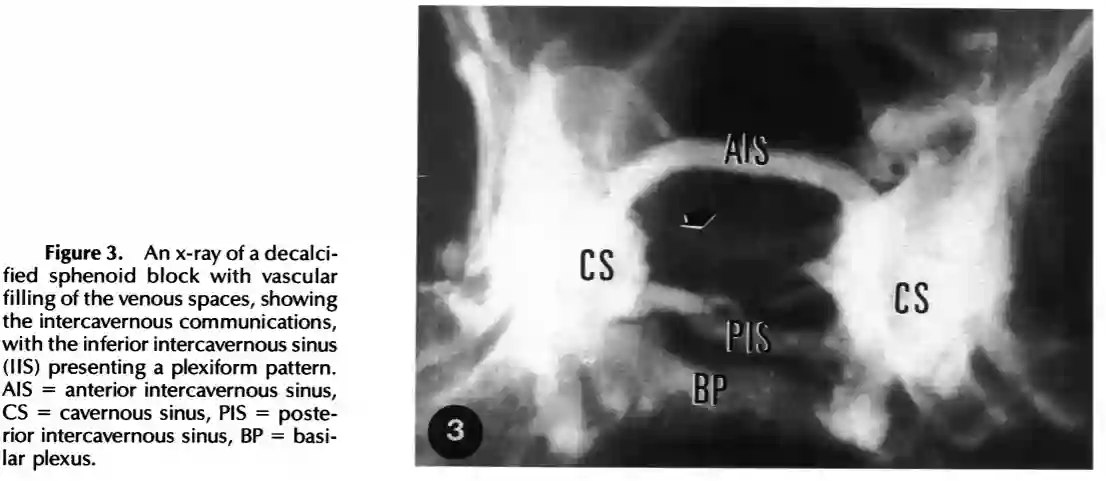

Anatomische Abbildung der Sella Region mit Darstellung des Sinus cavernosus anterior und inferior. Abbildung adaptiert von Albert Rhoton 2002 Neurosurgery.Abbildung des Sinus intercavernosus anterior und posterior. Adaptiert aus Aquini et al. 1994.

Abbildung des Sinus intercavernosus anterior und posterior. Adaptiert aus Aquini et al. 1994.